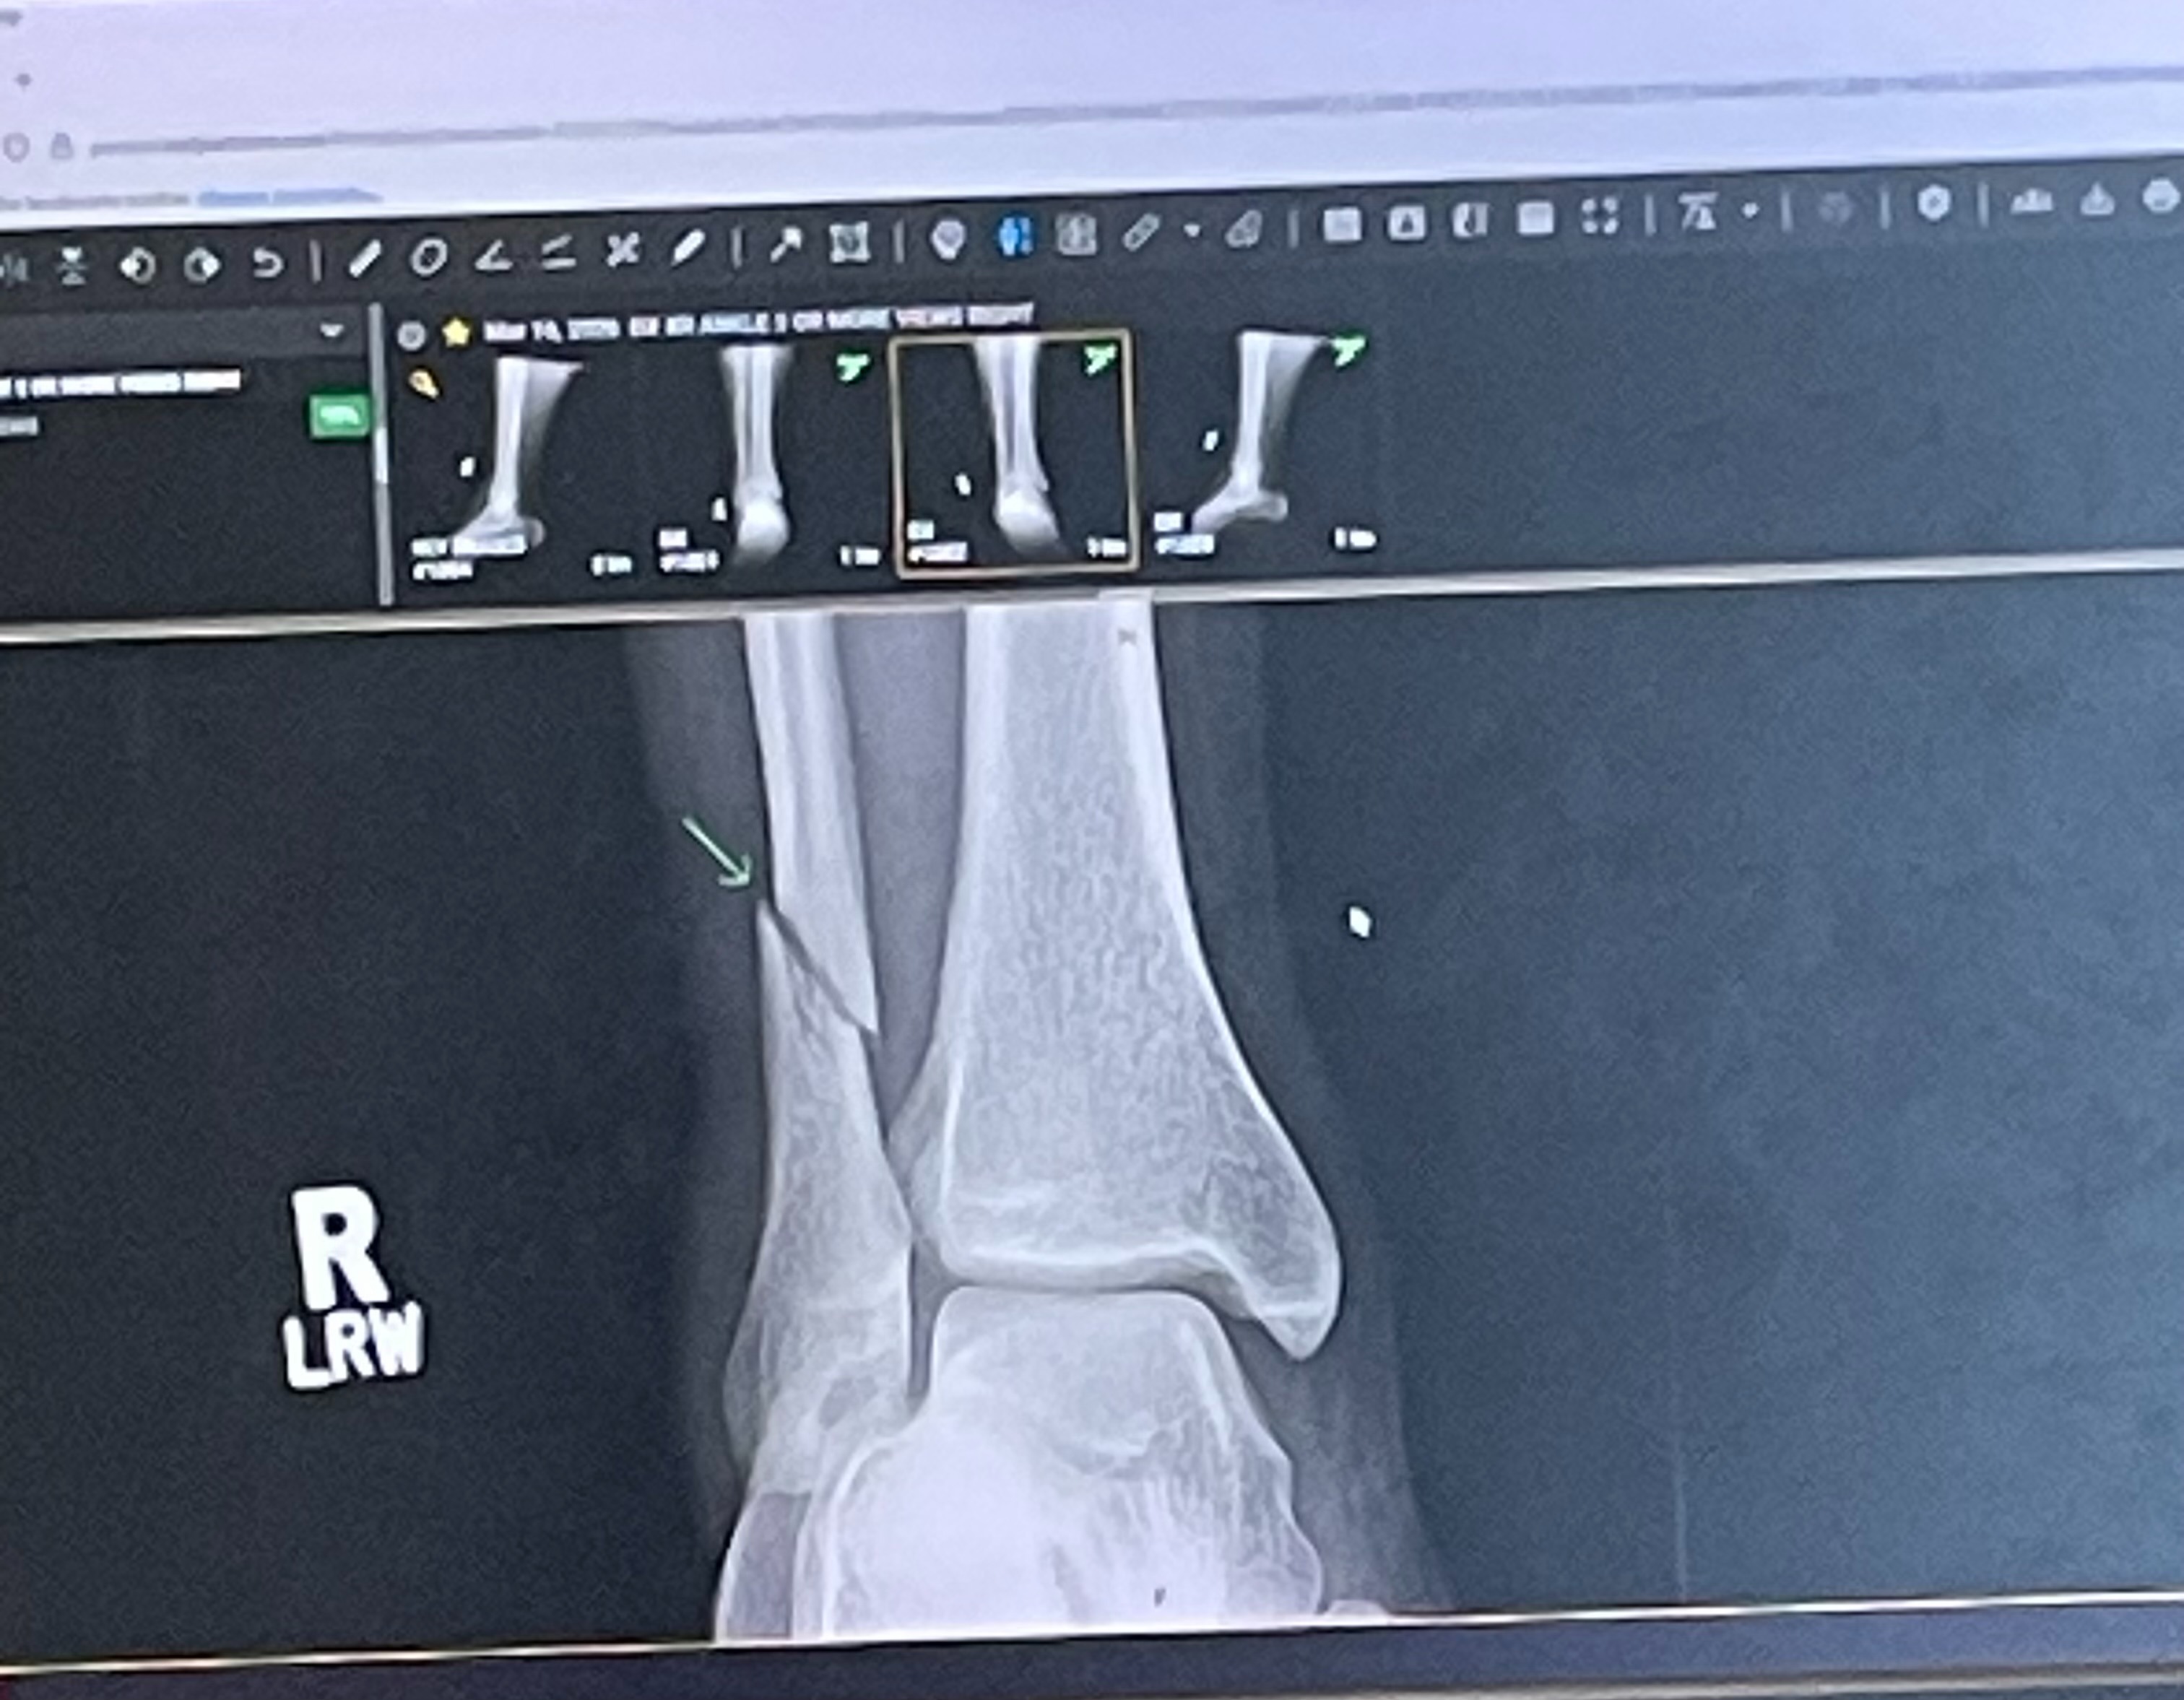

I recently sustained a fracture to my right fibula as a result of a hard fall I took on Saturday, 03/14/2026. This accident also caused a shift in my right talus that has left it in an unstable condition. In order for my leg to fully heal and prevent arthritis in the near future, I require surgery, which will take place on Tuesday, March 24th.